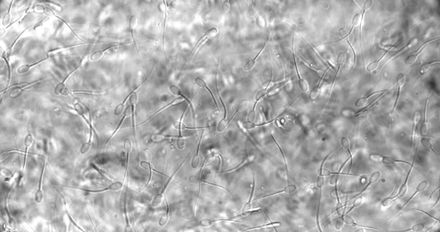

Forskare testar nytt hormonfritt preventivmedel för kvinnor Hindrar spermierna att nå ägget Forskare vid bland annat KTH, KI och Karolinska Universitetssjukhuset har kommit långt med testerna av ett nytt hormonfritt preventivmedel för kvinnor. Det handlar om en vaginal gel som stärker den naturliga barriär som finns i livmoderhalsen och på så vis hindrar spermierna att nå fram till ägget. Tester på får visar att gelen fungerar. Thomas Crouzier, forskare vid avdelning Glykovetenskap på KTH och ansvarig för arbetet säger följande: "Slembarriären är vanligtvis sluten och inte penetrerbar för spermier, men öppnar sig vid tidpunkten för ägglossning för att möjliggöra befruktning. Vi visar att med hjälp av en vaginal gel bestående av bland annat en polymer kan vi modifiera barriärens fysiska egenskaper och göra den ogenomtränglig för spermier. Vaginala geler som denna kan appliceras på några sekunder. Vi tänker oss att en sådan här produkt ska kunna användas från sekunder till någon timme innan sexuell umgänge. Effekten skulle då kunna bestå i timmar, men avta allt eftersom slembarriären byts ut på naturlig väg, och därmed också gelen." Läs mer på länken nedan. Tumnagel